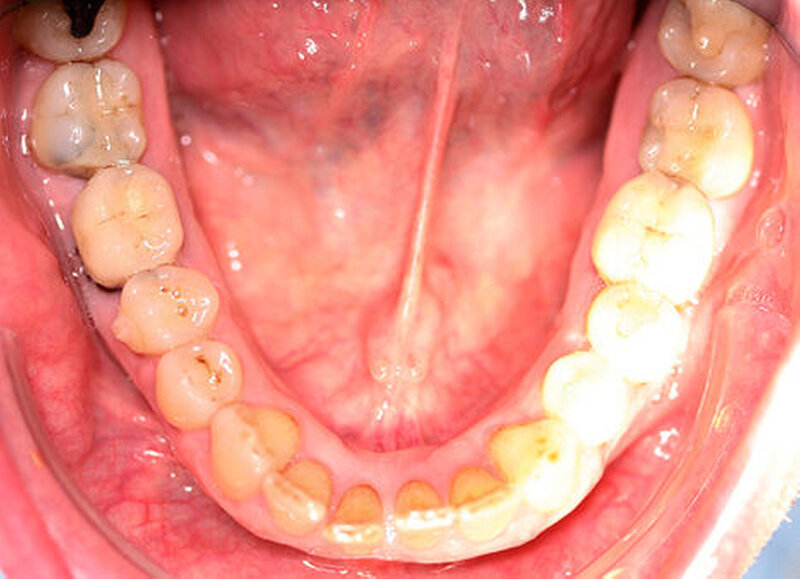

Anamnestisch lagen keine Besonderheiten vor. Es ist jedoch zu vermerken, dass ein regelmäßiger Alkohol-, Koffein- und Nikotinkonsum zugrunde lag. Intraoral zeigte sich ein bereits konservierend versorgtes permanentes Gebiss mit aktivem und inaktivem kariösen Geschehen. Große Anteile der Zahnhälse lagen nach Zahnfleischrückgang in Kombination mit Knocheneinbrüchen frei. Zahn 27 wurde bereits extrahiert.

Eine Beurteilung der parodontalen Situation an Zahn 11 offenbarte mesial und distal Sondierungstiefen von jeweils 6 mm.

Kieferorthopädisch imponierte beidseits eine neutrale Verzahnung bei einem tiefen Biss von 5 mm – bedingt durch die Verlängerung beider Frontzahngruppen. Besonders Zahn 11 zeigte eine erhebliche Verlängerung und Protrusion mit einer sagittalen Frontzahnstufe von 5 mm. Sowohl die Frontzähne im Ober- als auch im Unterkiefer wiesen eine lückige Beziehung zueinander auf (Abbildung 1).